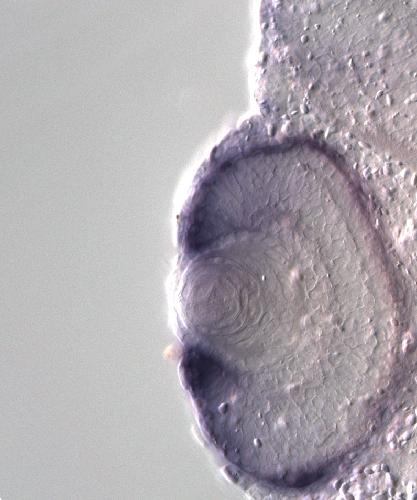

tpp1

tripeptidyl peptidase I

tpp1 encodes a lysosomal serine peptidase that removes N‑terminal tripeptides from substrates and contributes to lysosomal protein degradation. The protein localizes to lysosomal membranes and lumen an...[+]